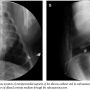

Next a 0.035˝, Rosen heavy-duty guidewire (William Cook Europe) was used to exchange the dilator of micropuncture set with a 7 Fr introducer sheath (Radifocus, Terumo Corporation). Through the introducer sheath, a 0.016˝ guidewire (Radifocus) was inserted into the pericardial space. The guidewire was looped superiorly and then inferiorly around the heart until the nearby region of the apex. Then a 6.4 Fr user attachable silicone catheter from a vascular access port set (ImPort, Medtronic, Inc) was placed over the guidewire to the guidewire tip. The guidewire and the sheath were removed, leaving the silicone catheter in place. A subcutaneous tunnel was established from the subxiphoid skin entry site to the left subaxillary area. The silicone catheter was placed through the tunnel and connected to a low profile port. A small incision was made and a subcutaneous pocket was created with blunt dissection. The port connected to the silicone catheter was placed in the pocket (Figure 2). The skin was closed. Fluoroscopy was performed when 5 mL of diluted contrast medium with saline solution was injected through the subcutaneous port to document the subcutaneous course and intrapericardial location of the silicone tube (Figure 3). The contrast medium injected into the pericardial space was immediately drained from the port. The color of contrast medium drained from the port was inspected to exclude the potential hemopericardium as a procedure-related complication. Chest fluoroscopy was also performed to check for occurrence of the pneumothorax.

Percutaneous pericardial access and subsequent silicone catheter implantation was successfully achieved in all 6 animals. The mean procedure duration was 55.3 ± 9.6 minutes and the mean radiation exposure time was 7.9 ± 1.9 minutes. Except for occasional premature ventricular contractions, no other complications, such as pneumothorax, hemopericardium, and fatal arrhythmia were encountered during the procedures. In the pig that was euthanized immediately after silicone catheter implantation, neither laceration of the pericardium at the entry site of the pericardial space nor gross injury of the nearby epicardium was noticed (Figure 4).